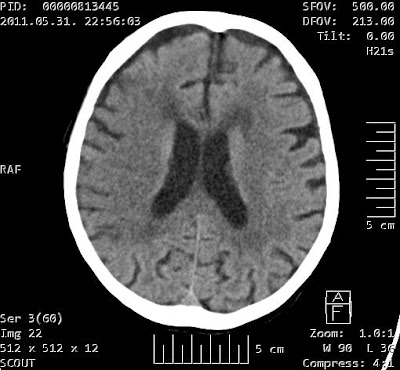

Ischaemiás stroke a jobb oldali a. cerebri media ellátási területén Szerző: admin | júl 6, 2011 | Brain | Nincsenek hozzászólások Az a. cerebri media területén az agyállomány hypodensebb az ellonoldalinál. Az intergyralis sulcusok keskenyebbek, a gyrusok kontúrja elmosott. A szürke és fehérállomány határa elmosott.